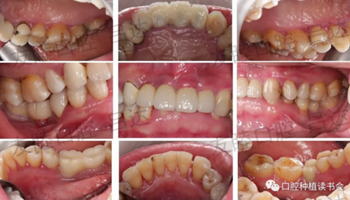

(1)初診:50歲女性患者,上頜中切牙及側(cè)切牙因齲壞缺失,植入3顆種植體;4單位聯(lián)冠完成修復(fù)。兩年后,因“種植體周圍黏膜反復(fù)水腫溢膿1個(gè)月”就診。(圖1)

圖1 初診口內(nèi)情況,可見種植體周圍黏膜腫脹明顯

檢查視角轉(zhuǎn)向整個(gè)口腔,發(fā)現(xiàn)有廣泛牙周感染。齦乳頭處可探及齦下牙石,探診深度PD:4-6mm,出血指數(shù)BI:3-4。(圖5-圖10)

圖5 口內(nèi)牙周情況